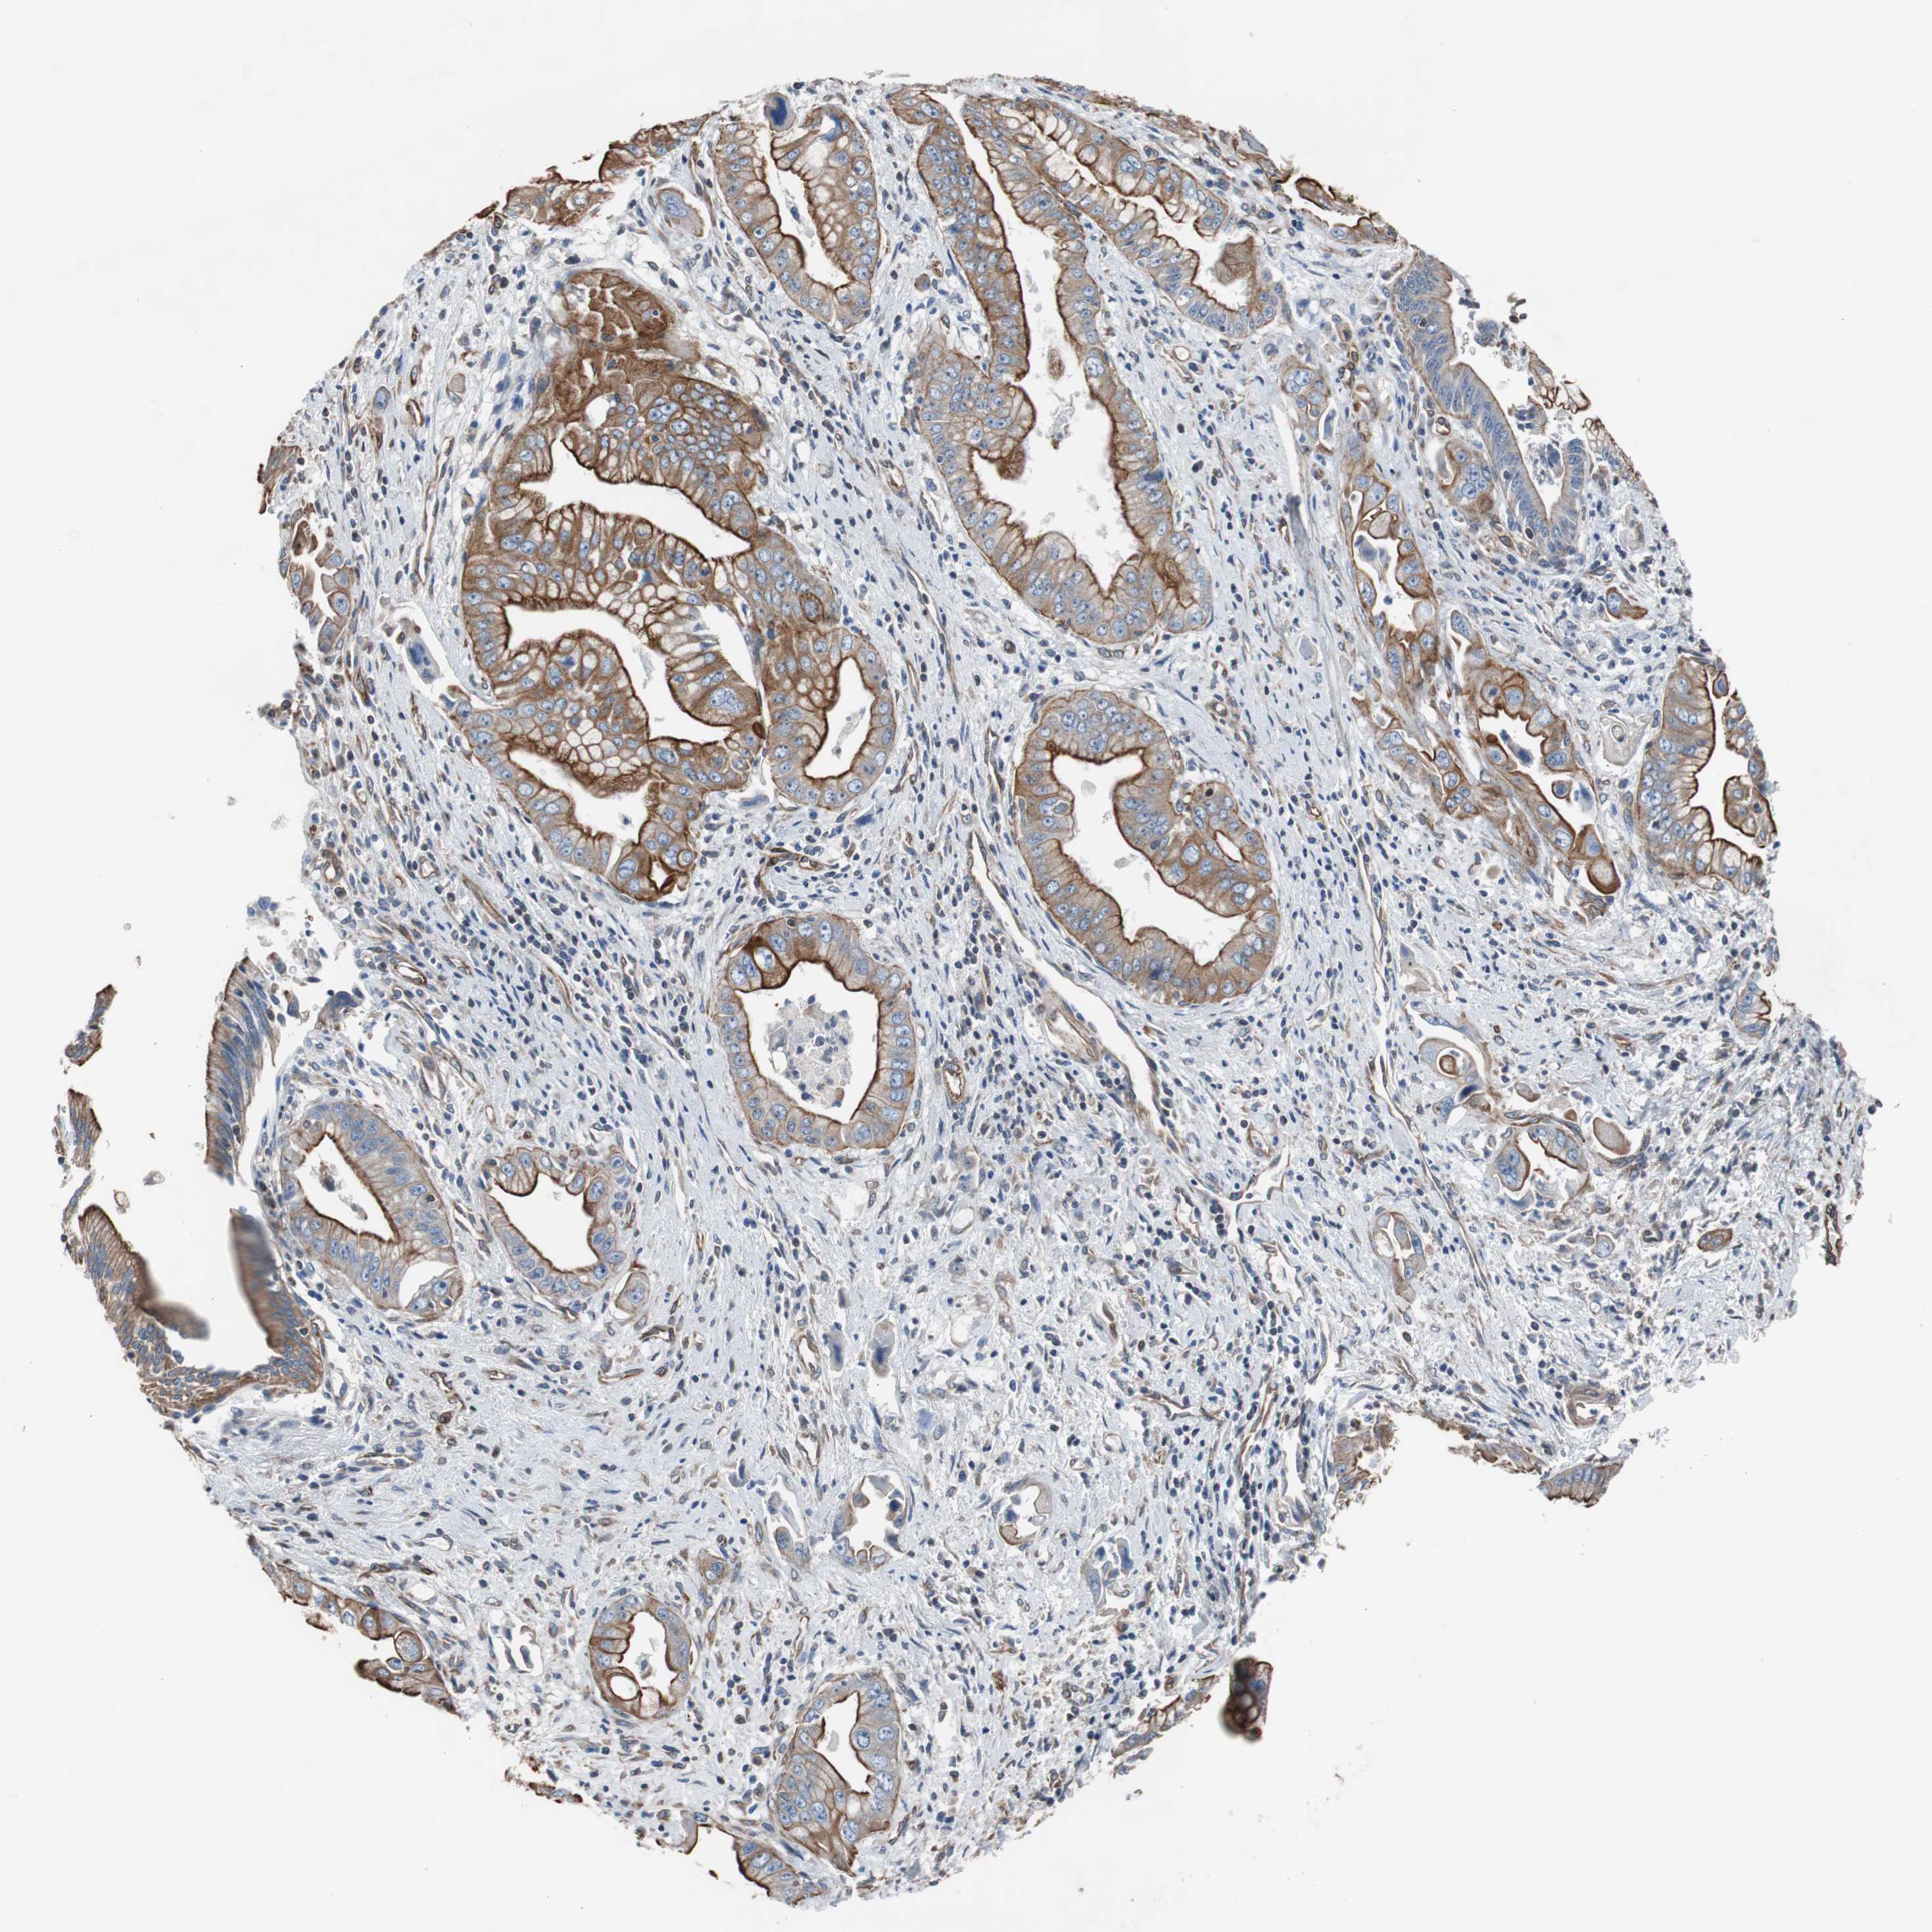

PANCREATIC CANCER - Protein expressioni

A mouse-over function shows sample information and annotation data. Click on an image to view it in a full screen mode. Samples can be filtered based on level of antibody staining by selecting one or several of the following categories: high, medium, low and not detected. The assay and annotation is described here.

Note that samples used for immunohistochemistry by the Human Protein Atlas do not correspond to samples in the TCGA dataset.

Antibody stainingi

Antibody staining in the annotated cell types in the current human tissue is reported as not detected, low, medium, or high, based on conventional immunohistochemistry profiling in selected tissues. This score is based on the combination of the staining intensity and fraction of stained cells.

Each image is clickable and will lead to virtual microscopy that enables deeper exploration of all samples and also displays staining intensity scores, fraction scores and subcellular localization as well as patient and tissue information for each sample.

Antibody HPA007119

Staining

High

Medium

Low

Not detected

Intensity

Strong

Moderate

Weak

Negative

Quantity

>75%

75%-25%

<25%

None

Location

Nuclear

Cytoplasmic/membranous

Cytoplasmic/membranous,nuclear

Adenocarcinoma, NOS

Adenocarcinoma, metastatic, NOS